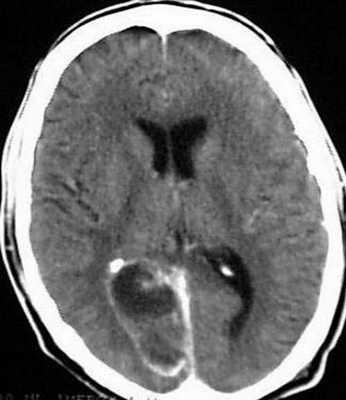

Рентгенография лёгких: без патологии. УЗИ органов брюшной полости: выявлены хронический холецистит, хронический панкреатит, диффузные изменения печени и поджелудочной железы. ЭКГ: в норме. На КТ головного мозга визуализировалось объёмное образование в правой лобной доли. Это вызвало подозрение на абсцесс, но отсутствие уровня жидкости, лихорадки и менингеального синдрома у пациентки в большей степени склонило клиническую мысль в сторону онкологического поражения. В связи с этим пациентку госпитализировали в отделении неврологии. Однако при осмотре онкологом и гинекологом данных, которые бы подтверждали наличие онкологии головного мозга, обнаружено не было. В качестве дообследования проведена КТ головного мозга с контрастным усилением. Она выявила объёмное образование в правой лобной доли с чётко очерченной капсулой. Рядом с образованием располагался отёк, срединные структуры были смещены влево примерно на 5 мм.

Точность диагностирования с помощью КТ головного мозга зависит от стадии формирования абсцесса. На ранних стадиях заболевания диагностика затруднена. На этапе раннего энцефалита (1-3 сутки) КТ определяет зону сниженной плотности неправильной формы. Введенное контрастное вещество накапливается неравномерно, преимущественно периферических отделах очага, реже в центре.

На более поздних этапах энцефалита контуры очага приобретают ровные округлые очертания. Контрастное вещество распределяется равномерно, по всей периферии очага; плотность центральной зоны очага при этом не меняется. Однако на повторной КТ (через 30-40 минут) определяется диффузия контраста в центр капсулы, а также наличие его и в периферической зоне, что не характерно для злокачественных новообразований.

Инкапсулированный абсцесс мозга на КТ имеет вид округлого объемного образования с четкими ровными контурами повышенной плотности (фиброзная капсула). В центре капсулы зона пониженной плотности (гной), по периферии видна зона отека. Введенное контрастное вещество накапливается в виде кольца (по контуру фиброзной капсулы) с небольшой прилежащей зоной глиоза.

На повторной КТ (через 30-40 минут) контрастное вещество не определяется. При исследовании результатов компьютерной томографии следует учесть, что противовоспалительные препараты (глюкокортикостероиды, салицилаты) в значительной степени влияют на скопление контраста в энцефалитическом очаге.